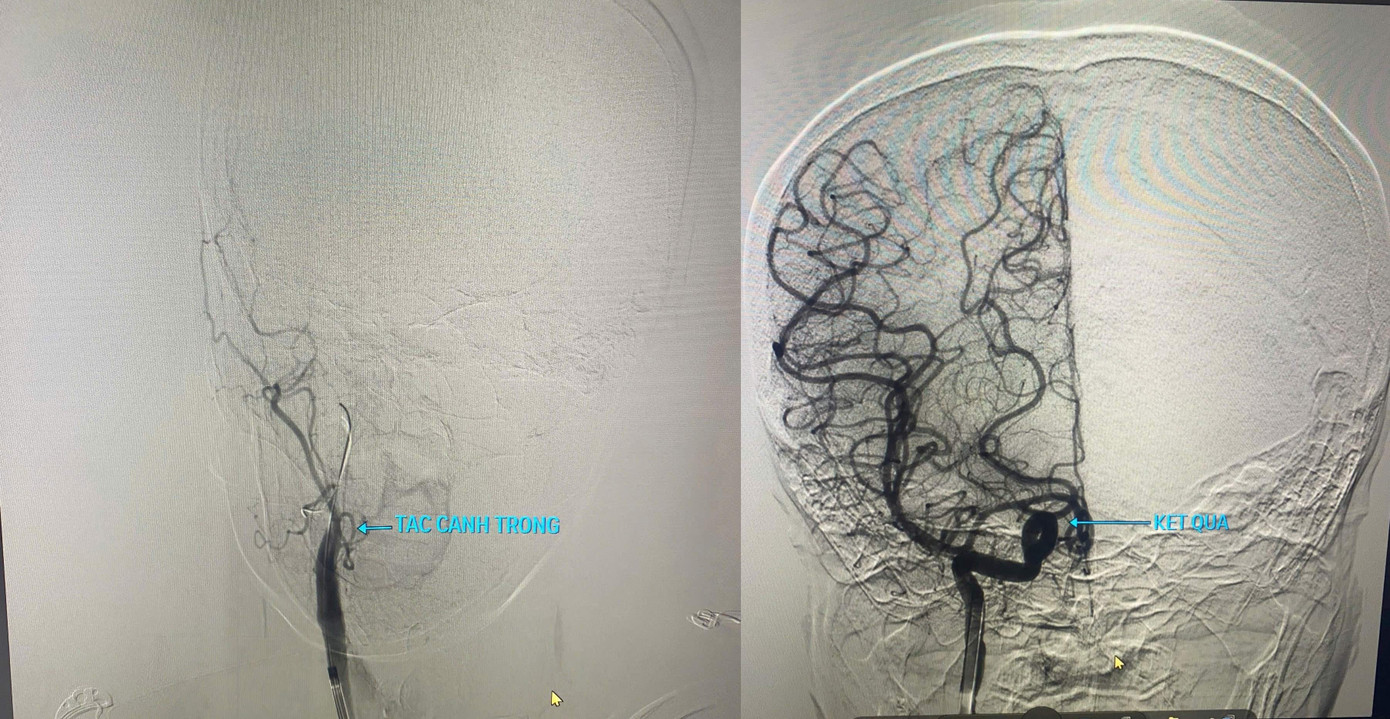

Hình ảnh tắc động mạch cảnh trong phải trước và sau can thiệp.